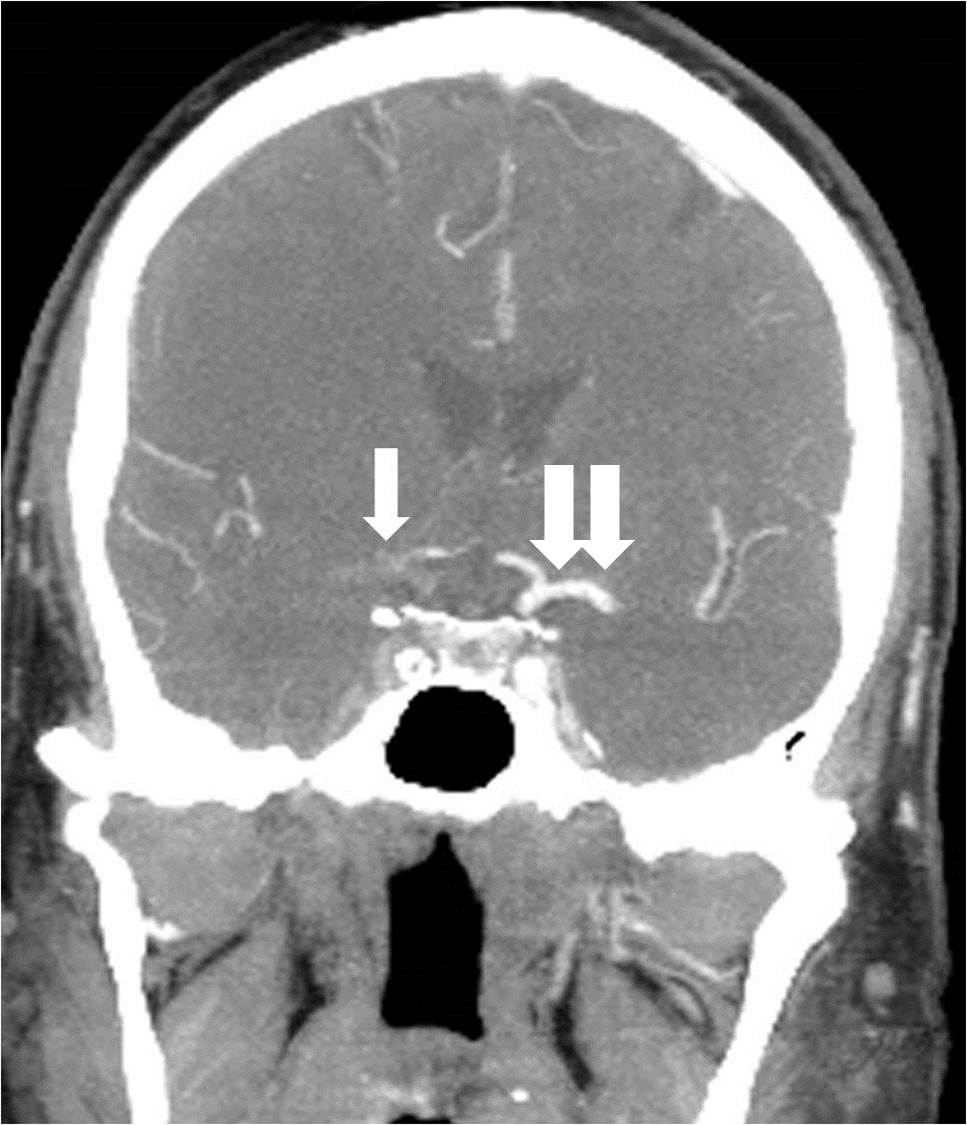

A 64-year-old man with a history of smoking and rheumatoid arthritis (RA) presented with left hemiparesis, slurred speech, and left facial droop. His NIHSS score was 9. Initial CTA showed occlusion of the extracranial right ICA and a tandem occlusion of the right MCA (Figure 5).